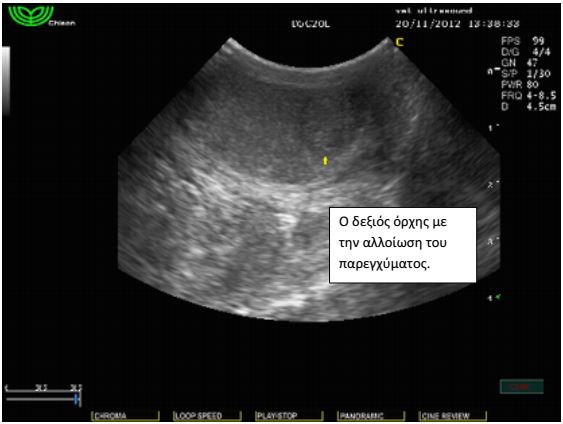

Σε γενική εξέταση αίματος κατά τον ετήσιο προληπτικό έλεγχο βρέθηκε ήπια μείωση του αιματοκρίτη και μέτρια αύξηση των λευκών αιμοσφαιρίων.Έγινε υπέρηχος κοιλίας όπου και διαπιστώθηκε ήπια διόγκωση του προστάτη αδένα. Τα υποσφυικά λεμφογάγγλια δεν βρέθηκαν διογκωμένα. Τα υπόλοιπα όργανα ήταν εντός των φυσιολογικών ορίων και χωρίς απώλεια της φυσιολογικής δομής τους. Στο παρέγχυμα των όρχεων εντοπίστηκαν αλλοιώσεις σαφώς περιγεγραμμένες με υποηχογενή άλω. Το FNB( fineneedlebiopsy) των αλλοιώσεων αποκάλυψε πως πρόκειται για μια νεοπλασματική εξεργασία των όρχεων, το σερτολίωμα. Οι αλλοιώσεις αυτές παράγουν οιστρογόνα και για το λόγο αυτό, μακροπρόθεσμα, μπορούν να προκαλέσουν απλασία του μυελού των οστών και μείωση του αιματοκρίτη. Το περιστατικό αντιμετωπίστηκε με ορχεκτομή. Μετά από λίγους μήνες οι αλλοιώσεις του προστάτη υποχώρησαν και η τιμή του αιματοκρίτη αποκαταστάθηκε στα φυσιολογικά επίπεδα